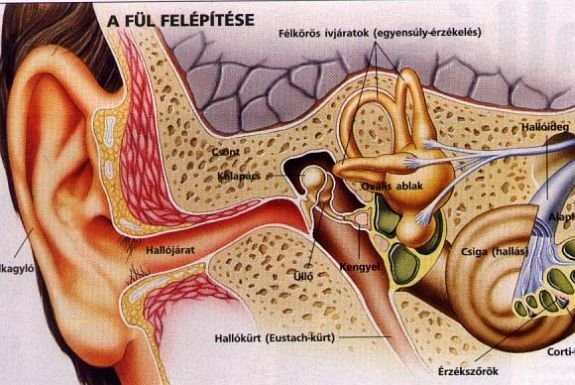

A füljárat az agy alatt helyezkedik el. Ha - a ledes megvilágítás helyett egy képzeletbeli tűt szúrnánk át a koponyán a két füljárat között, akkor az talán éppen súrolná az agyalapot, de a nagyagyat, vagy más agyterületet jócskán elkerülné. Lásd a jobboldali képet!

A füljárat az agy alatt helyezkedik el. Ha - a ledes megvilágítás helyett egy képzeletbeli tűt szúrnánk át a koponyán a két füljárat között, akkor az talán éppen súrolná az agyalapot, de a nagyagyat, vagy más agyterületet jócskán elkerülné. Lásd a jobboldali képet!- Probléma még, hogy - az intuícióval ellentétben - a füljárat végén bonyolult és igen vastag a koponya (nem véletlenül sziklacsont a neve); jóval vastagabb, mint akárhol a hajunk fedte koponyarészen. Az alsó kép (amelyet egy a fül betegségeiről szóló cikkből idézünk ide be) jól mutatja, hogy a füljárat ugyan kissé felfele hatol, de mögötte vastag csontozat foglalja magába a hang-, helyzet- és gyorsulásingerek feldolgozását végző receptorokat.